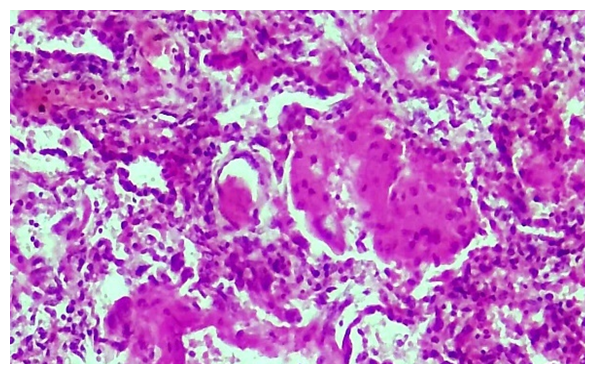

Microscopically, it is determined that distelectase has developed and thickened diffusely in the lung alveolar tissue, that is, the cavity and wall of the alveoli are not differentiated, and have become a single airless tissue. In this case, all the branches of the pulmonary artery are enlarged, full, blood is poured around it.During the proliferative period of the COVID-19 infection, initial changes are observed in the blood vessel wall. Vascular endothelium is desquamated, hypertrophied and atrophied due to endotheliosis and endotheliitis, and the basal membrane is exposed. Due to the development of the process of disorganization in the basal membrane, it is determined that fibrinoid bending and fibrinoid necrosis have occurred, it has become homogenized, some areas have hyperchromasia, and it is destroyed. The pericyte cells around the vessel wall are activated and proliferated, their nuclei become hypertrophied and hyperchromic. It is observed that scattered lymphoid infiltration appeared around the vessel and in the wall tissue between the alveoli (Fig. 3). Fibrinoid swelling and fibrinoid necrosis are also found in the fibrous structures of the alveolar wall. | Figure 3. Proliferation of lymphohistiocytic cells in the walls of pulmonary blood vessels and alveoli during the proliferative period of COVID-19. Stain: H-E. size: 10x40 |